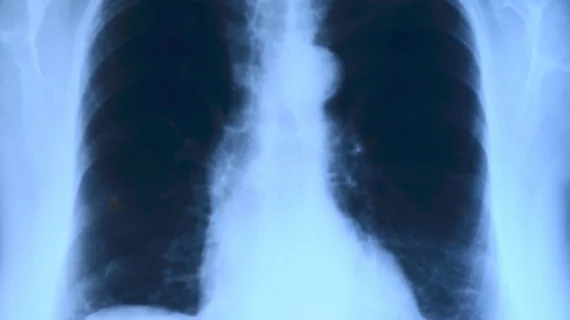

A deep-learning algorithm was significantly faster and just as accurate as most radiologists in analyzing chest X-rays for several diseases, according to a study led by Stanford University researchers. Based on the findings, radiologists may soon be able to interpret chest X-rays and diagnose diseases for patients at a much quicker pace.

Stanford researchers developed a convolutional neural network, called the CheXNeXt, to detect the presence of 14 different pathologies, including pneumonia, pleural effusion, pulmonary masses and chest X-rays, according to the study published in PLOS Medicine. The deep-learning algorithm was trained and validated on a set of 420 images. Its performance was later compared to nine radiologists using the area under the receiver operating characteristic curve (AUC), which illustrates the accuracy and diagnostic ability of a binary classifier system.

Chest X-ray interpretation is critical for the detection of thoracic diseases, like tuberculosis and lung cancer, according to researchers. However, the task is typically consuming and requires expert radiologists to read the images.